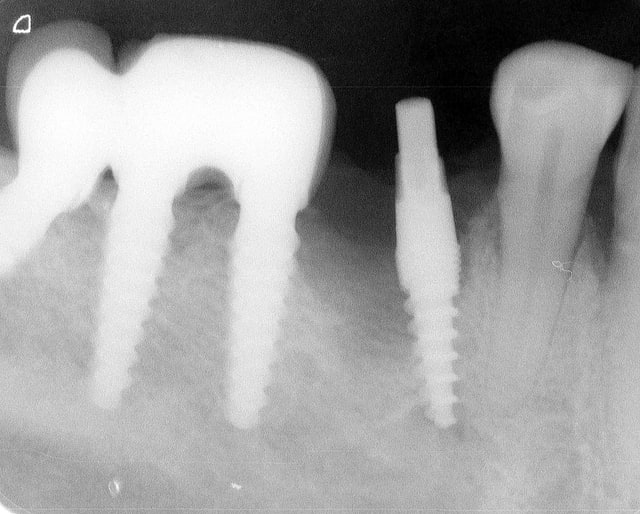

Pour ceux que ca interessent, et parce qu on a m a demandé des cas supplémentaires dans le sujet 23 implants rehabilitation totale, voici un autre cas d implantation immédiate avec la technique minimalement invasive et condensation grace aux forets.

Le patient a reçu un traitement il y a dix ans dans le maxillaire et dans le 4eme quadrant.Comme on peut le voir j´ai du extraire quelques dents au maxillaire: 35 37 et 45.

Le septum de la 37 a été foré avec un foret conique 3 faces.

J ai planté à 60 Ncm sans fracturer le septum.Juste après l opération , les prep caps en zircon ont été cémenté.La restauration définitive 34 jusqu` à 37 été fixé 2 semaines après l implantation avec implantlink (detax). Après un an, le bridge a été retiré facilement pour voir l´état de la gencive et faire une radio de contrôle.On la re ossifiction est satisfaisante et que la gencive "aime" le zircon.

Le bridge a ensuite été recémenté sans correction nécessaire du bridge.